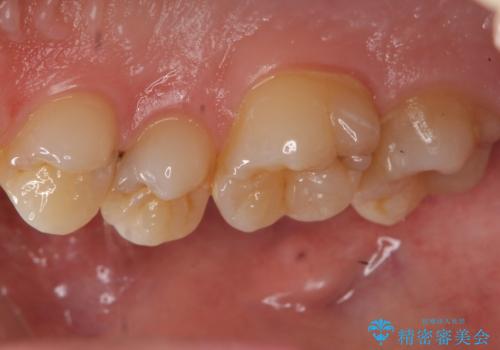

歯と歯の間の虫歯 セラミックインレーでの治療

- 検査の結果左上の歯と歯の間に虫歯が発見された患者様です。

虫歯の除去後セラミックインレーでの修復処置をしていきます。

歯と歯の間は虫歯の好発部位とされています。

適合の良いインレーでの修復をすることで再発を防止します。